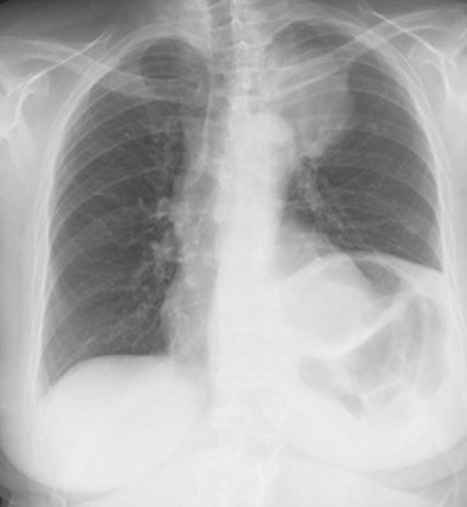

**Heart failure** Alveolar batwing shadowing Kerley B lines Cardiomegaly Upper lobe Diversion Pleural Effusion

39